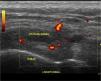

En estas condiciones se explora al paciente por primera vez mediante un examen ecográfico donde se observaba que el tendón de la pata de ganso perdía su aspecto fibrilar, alcanzando un mayor grosor y tomando un aspecto predominantemente hipoecoico (figura 1). Además al examinarlo en un plano axial, el tendón aparecía rodeado de un halo hipoecoico que lo envolvía parcialmente3,4 (figura 2). Sin embargo la exploración ultrasónica de la inserción a nivel de la tibia, presentaba un patrón fibrilar normal (figura 3). Por tanto con el estudio ecográfico se demuestra que se trata de una tendinopatía de la pata de ganso.

Figura 1. En un corte longitudinal realizado sobre la pata de ganso en la zona de ecopalpación positiva, se aprecia su aspecto hipoecoico. Aplicando el Doppler Potencia se observa un aumento de la vascularización.